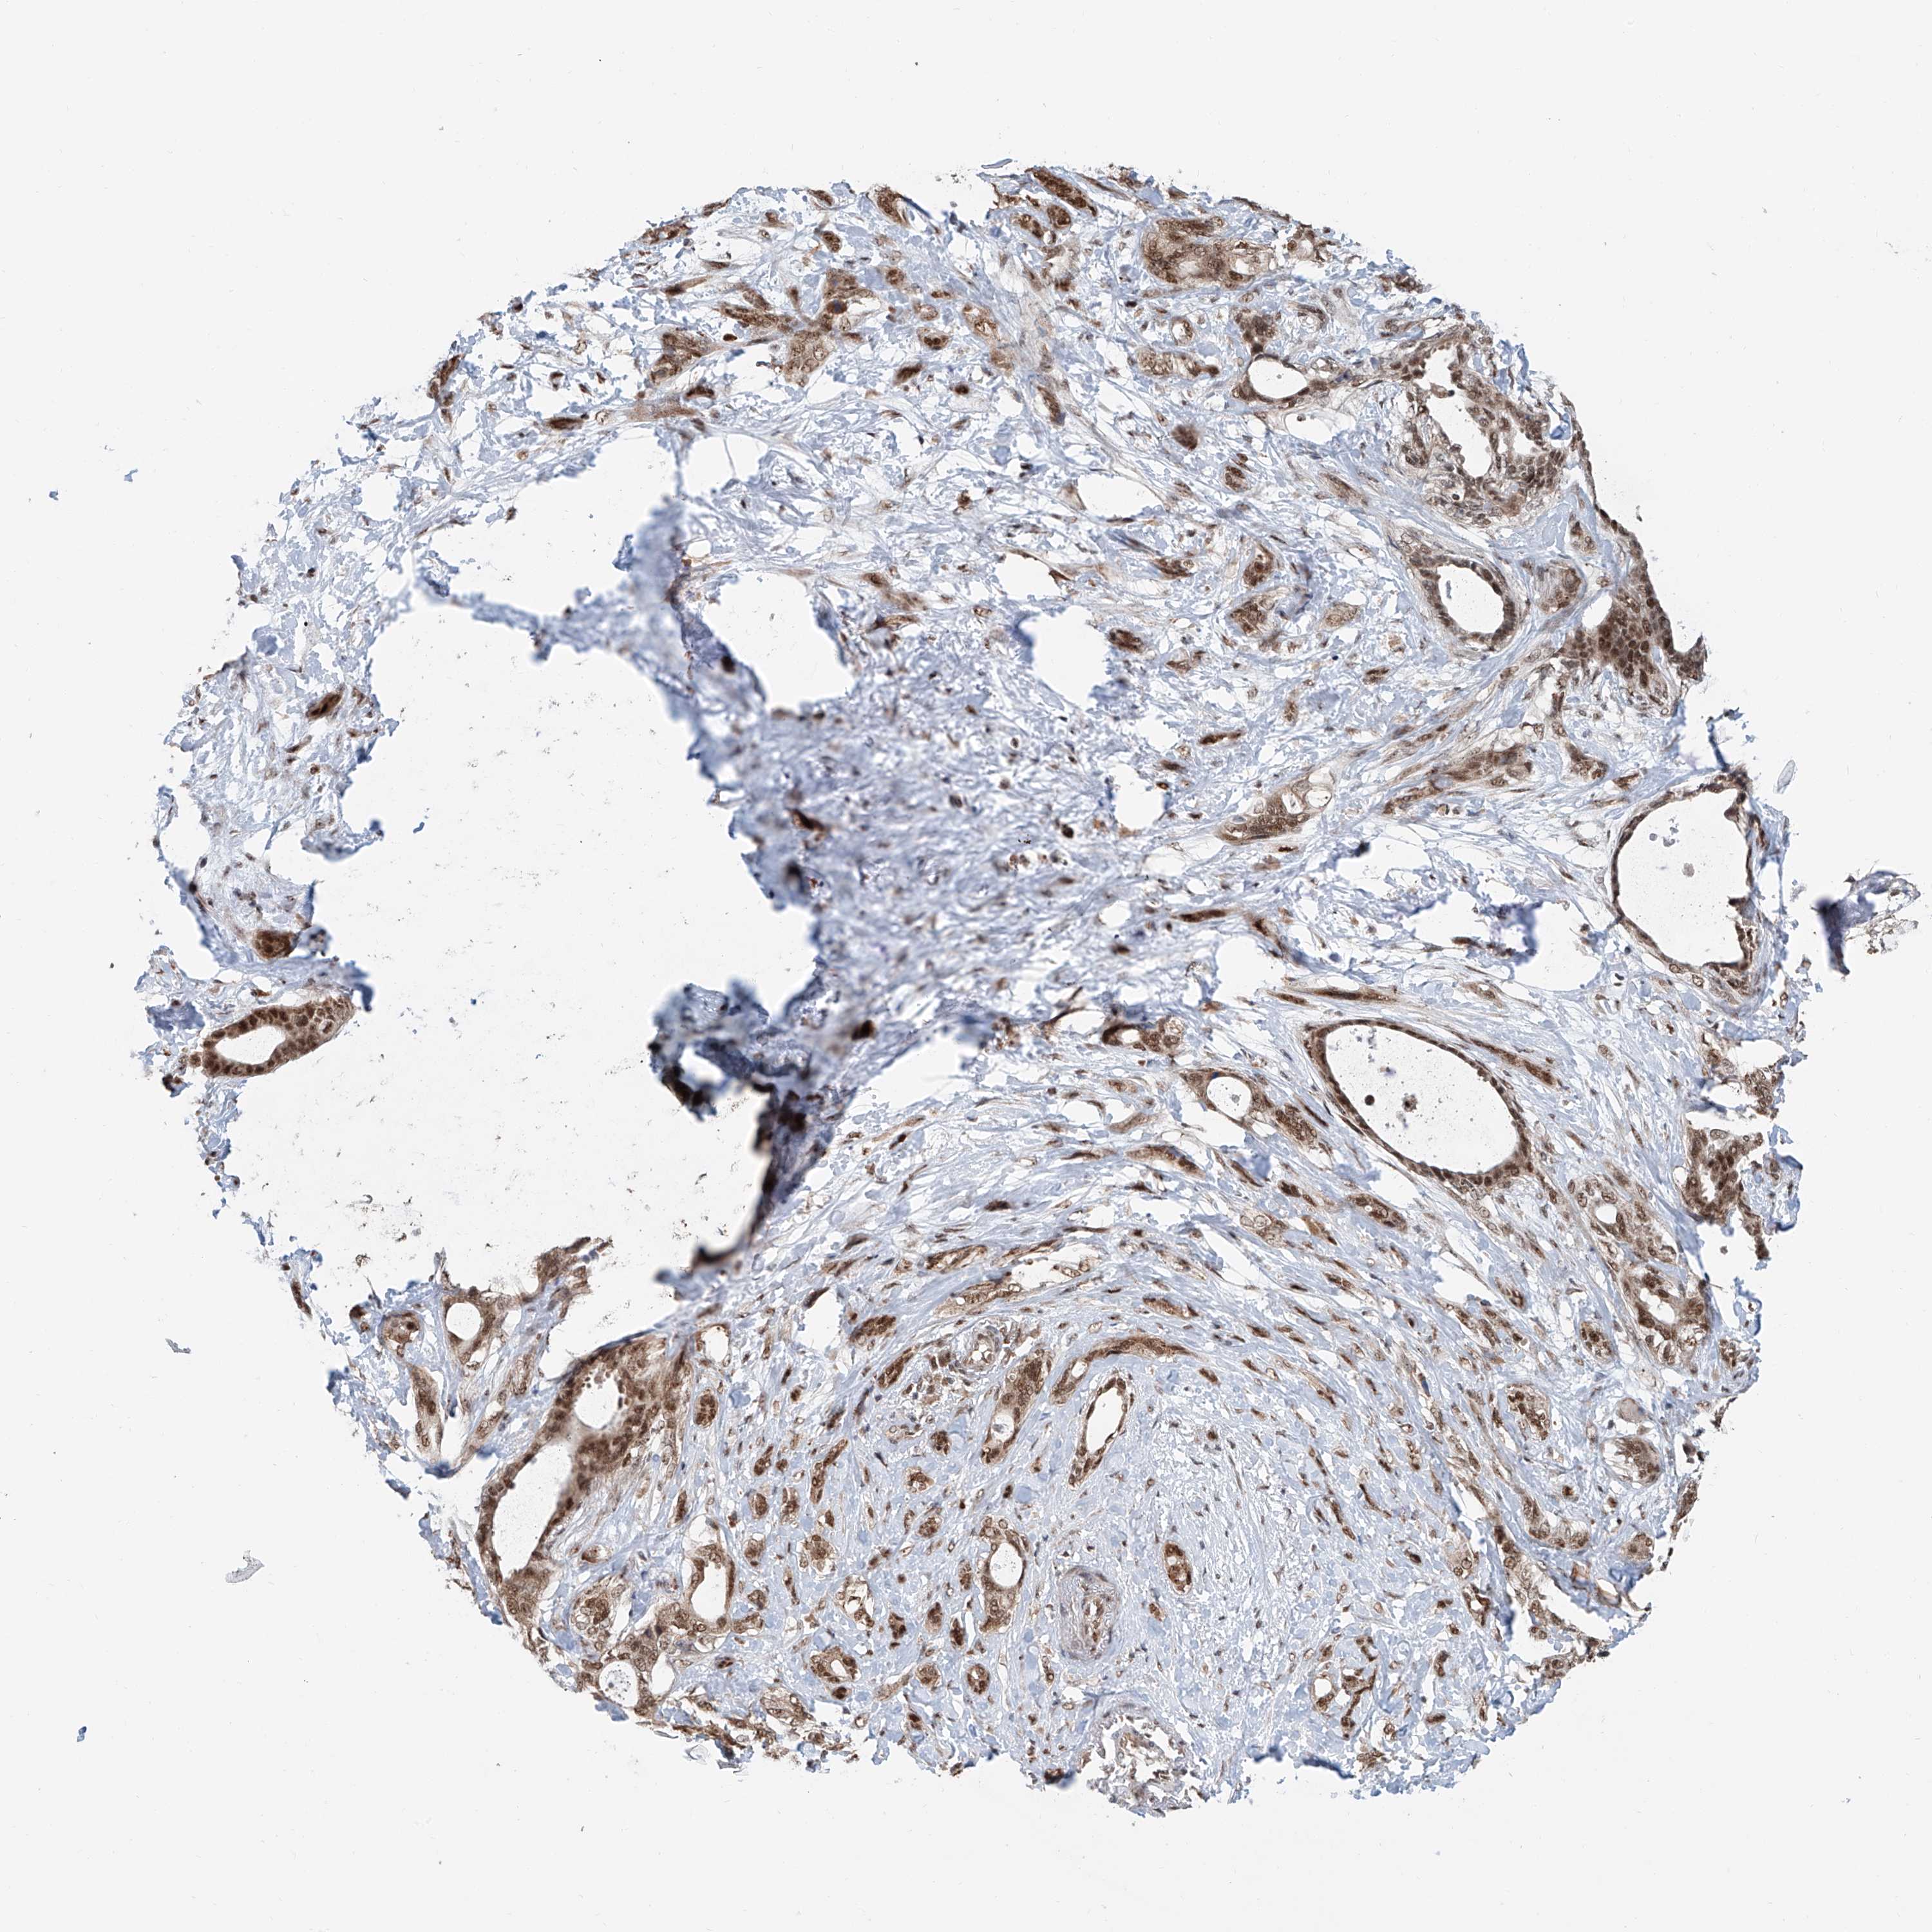

PANCREATIC CANCER - Protein expressioni

A mouse-over function shows sample information and annotation data. Click on an image to view it in a full screen mode. Samples can be filtered based on level of antibody staining by selecting one or several of the following categories: high, medium, low and not detected. The assay and annotation is described here.

Note that samples used for immunohistochemistry by the Human Protein Atlas do not correspond to samples in the TCGA dataset.

Antibody stainingi

Antibody staining in the annotated cell types in the current human tissue is reported as not detected, low, medium, or high, based on conventional immunohistochemistry profiling in selected tissues. This score is based on the combination of the staining intensity and fraction of stained cells.

Each image is clickable and will lead to virtual microscopy that enables deeper exploration of all samples and also displays staining intensity scores, fraction scores and subcellular localization as well as patient and tissue information for each sample.

Antibody HPA028467

Antibody HPA031255

Antibody HPA031256

Staining

Adenocarcinoma, NOS